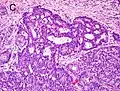

Gleason score 9 (4+5) with cribriform glands, some with necrosis -

Gleason score 10 (5+5) with cords of cells -

Gleason score 10 (5+5) with individual cells -

Gleason score 10 (5+5) with solid sheets of cells

Gleason 5

Neoplasms have no glandular differentiation (thus not resembling normal prostate tissue at all). It is composed of sheets (groups of cells almost planar in appearance (like the top of a box), solid cords (group of cells in a rope like fashion running through other tissue/cell patterns seen), or individual cells. You should not see round glands with lumenal spaces that can be seen in the other types that resemble more the normal prostate gland appearance.[4][7]